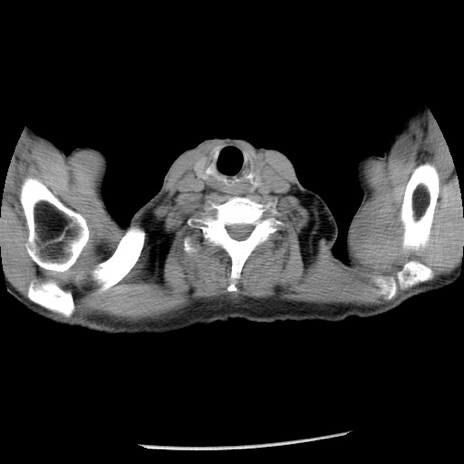

症例26(横断像)

【症例】80歳代男性

【主訴】嘔吐

【現病歴】昨晩2回嘔吐あり、今朝になっても嘔吐あり。来院。

【既往歴】胃潰瘍

【身体所見】意識清明、BT 37.6℃、BP 166/95mmHg、HR 100bpm、SpO2 97%、腹部:平坦・軟、腸蠕動音聴取良好、圧痛なし。

【データ】WBC 21900、CRP 1.46